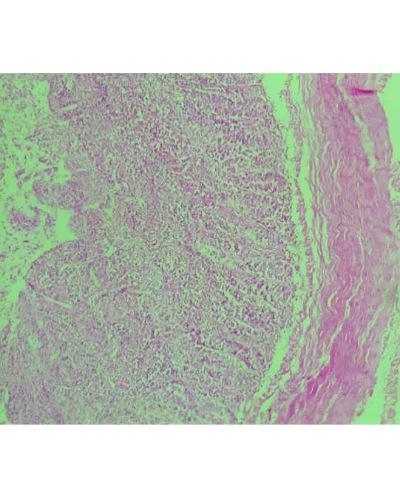

The Biochemical and Histopathological Effects of Methanolic Extract of Banana Flower (Musa Acuminata) in Albino Rats.